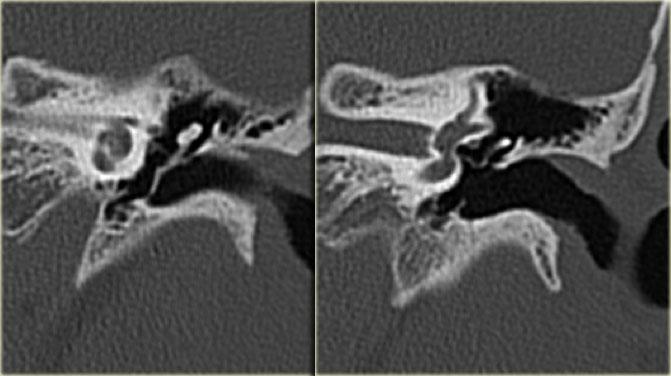

Gãy dọc (mũi tên vàng) đi qua xương chũm về phía vùng hạch gối. Trật xương đe với trật khớp búa-đe và khớp đe-bàn đạp (mũi tên xanh).

Hình ảnh bên trái của một nam bệnh nhân bị chấn thương đầu hai tháng trước.

Bệnh nhân than phiền về ù tai từng cơn.

Có đường gãy dọc (mũi tên vàng) đi qua xương chũm về phía vùng hạch gối.

Có trật xương đe với trật khớp búa-đe và khớp đe-bàn đạp (mũi tên xanh).

Không có tổn thương tai trong.

Tai trái để so sánh.